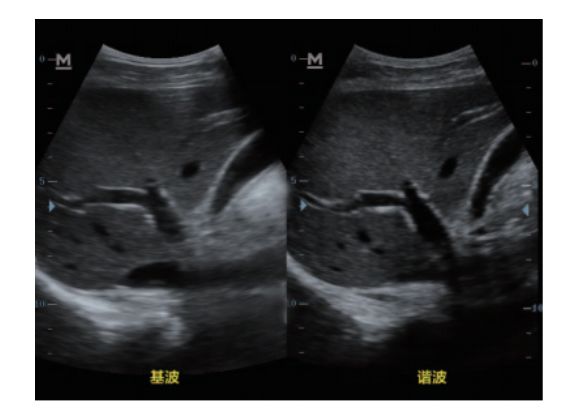

设备型号DP-50 全自动便携式超声诊断系统(迈瑞),该设备为DP 系列超声的较高级版本,具有iTouch 图像一键优化、 iBeam 复合成像、iClear 斑点噪声抑制、宽带频移谐波等技术。

宽带频移谐波技术: